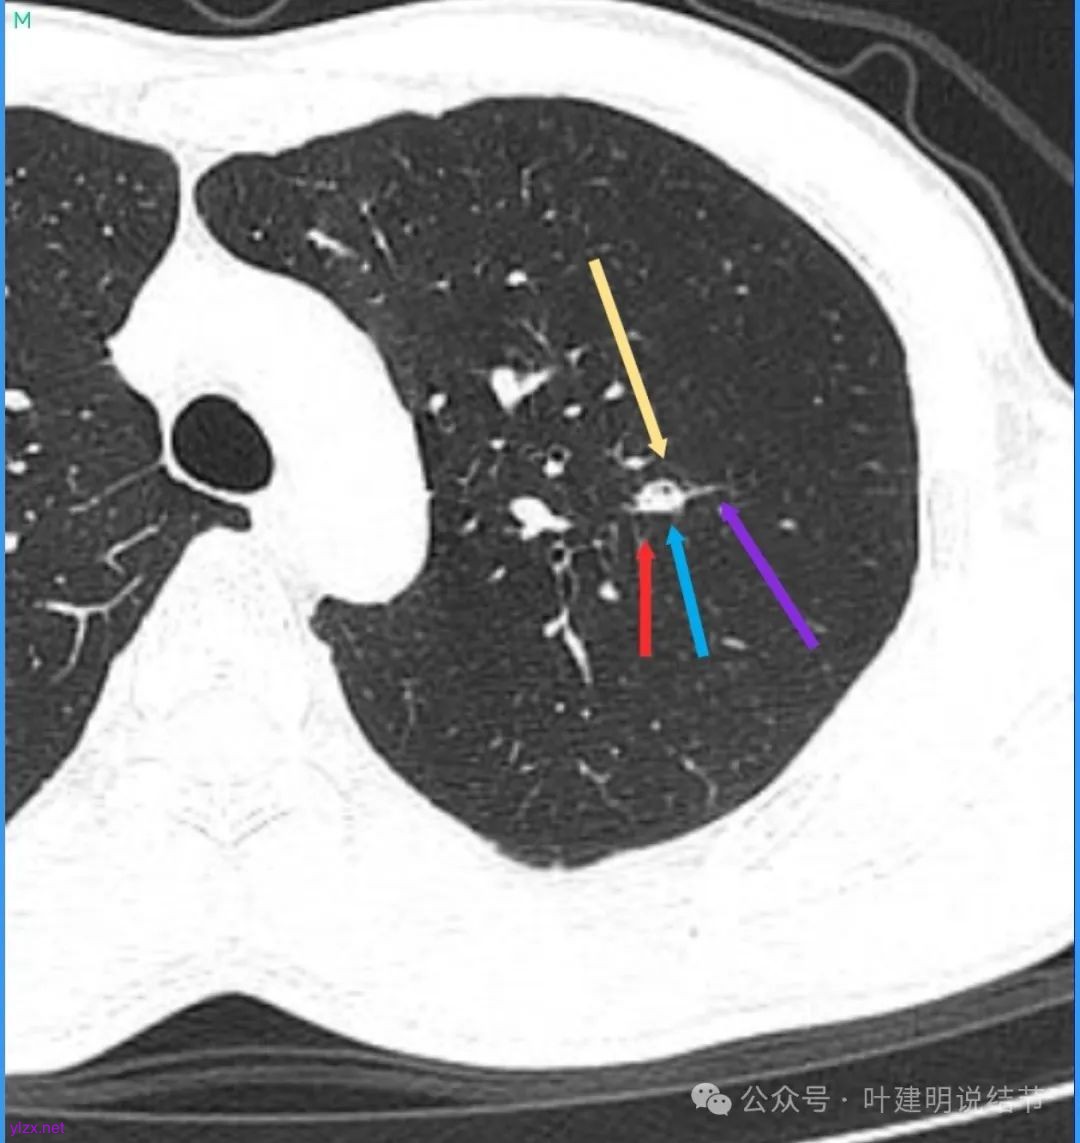

病灶密度不均,混合密度的样子,相应的细支气管有扭曲略显扩张。

边缘较为毛糙不平,灶内密度杂乱,细支气管穿行,整体轮廓较清。

邻近血管受结节影响,略向病灶侧弯,病灶处是扩张的细支气管还是灶内的空泡征?

有血管征,整体轮廓与边界较清,灶内有蜂窝状。

血管穿过病灶,灶内多个小空泡,整体轮廓较清。

蓝色部分似乎是血管,但似乎又是增厚的支气管壁,局部细支气管扩张。

特别上上图边缘些的层面,蓝色箭头所指的实性明显又像位于扩张细支气管内或与支气管壁一块的样子。